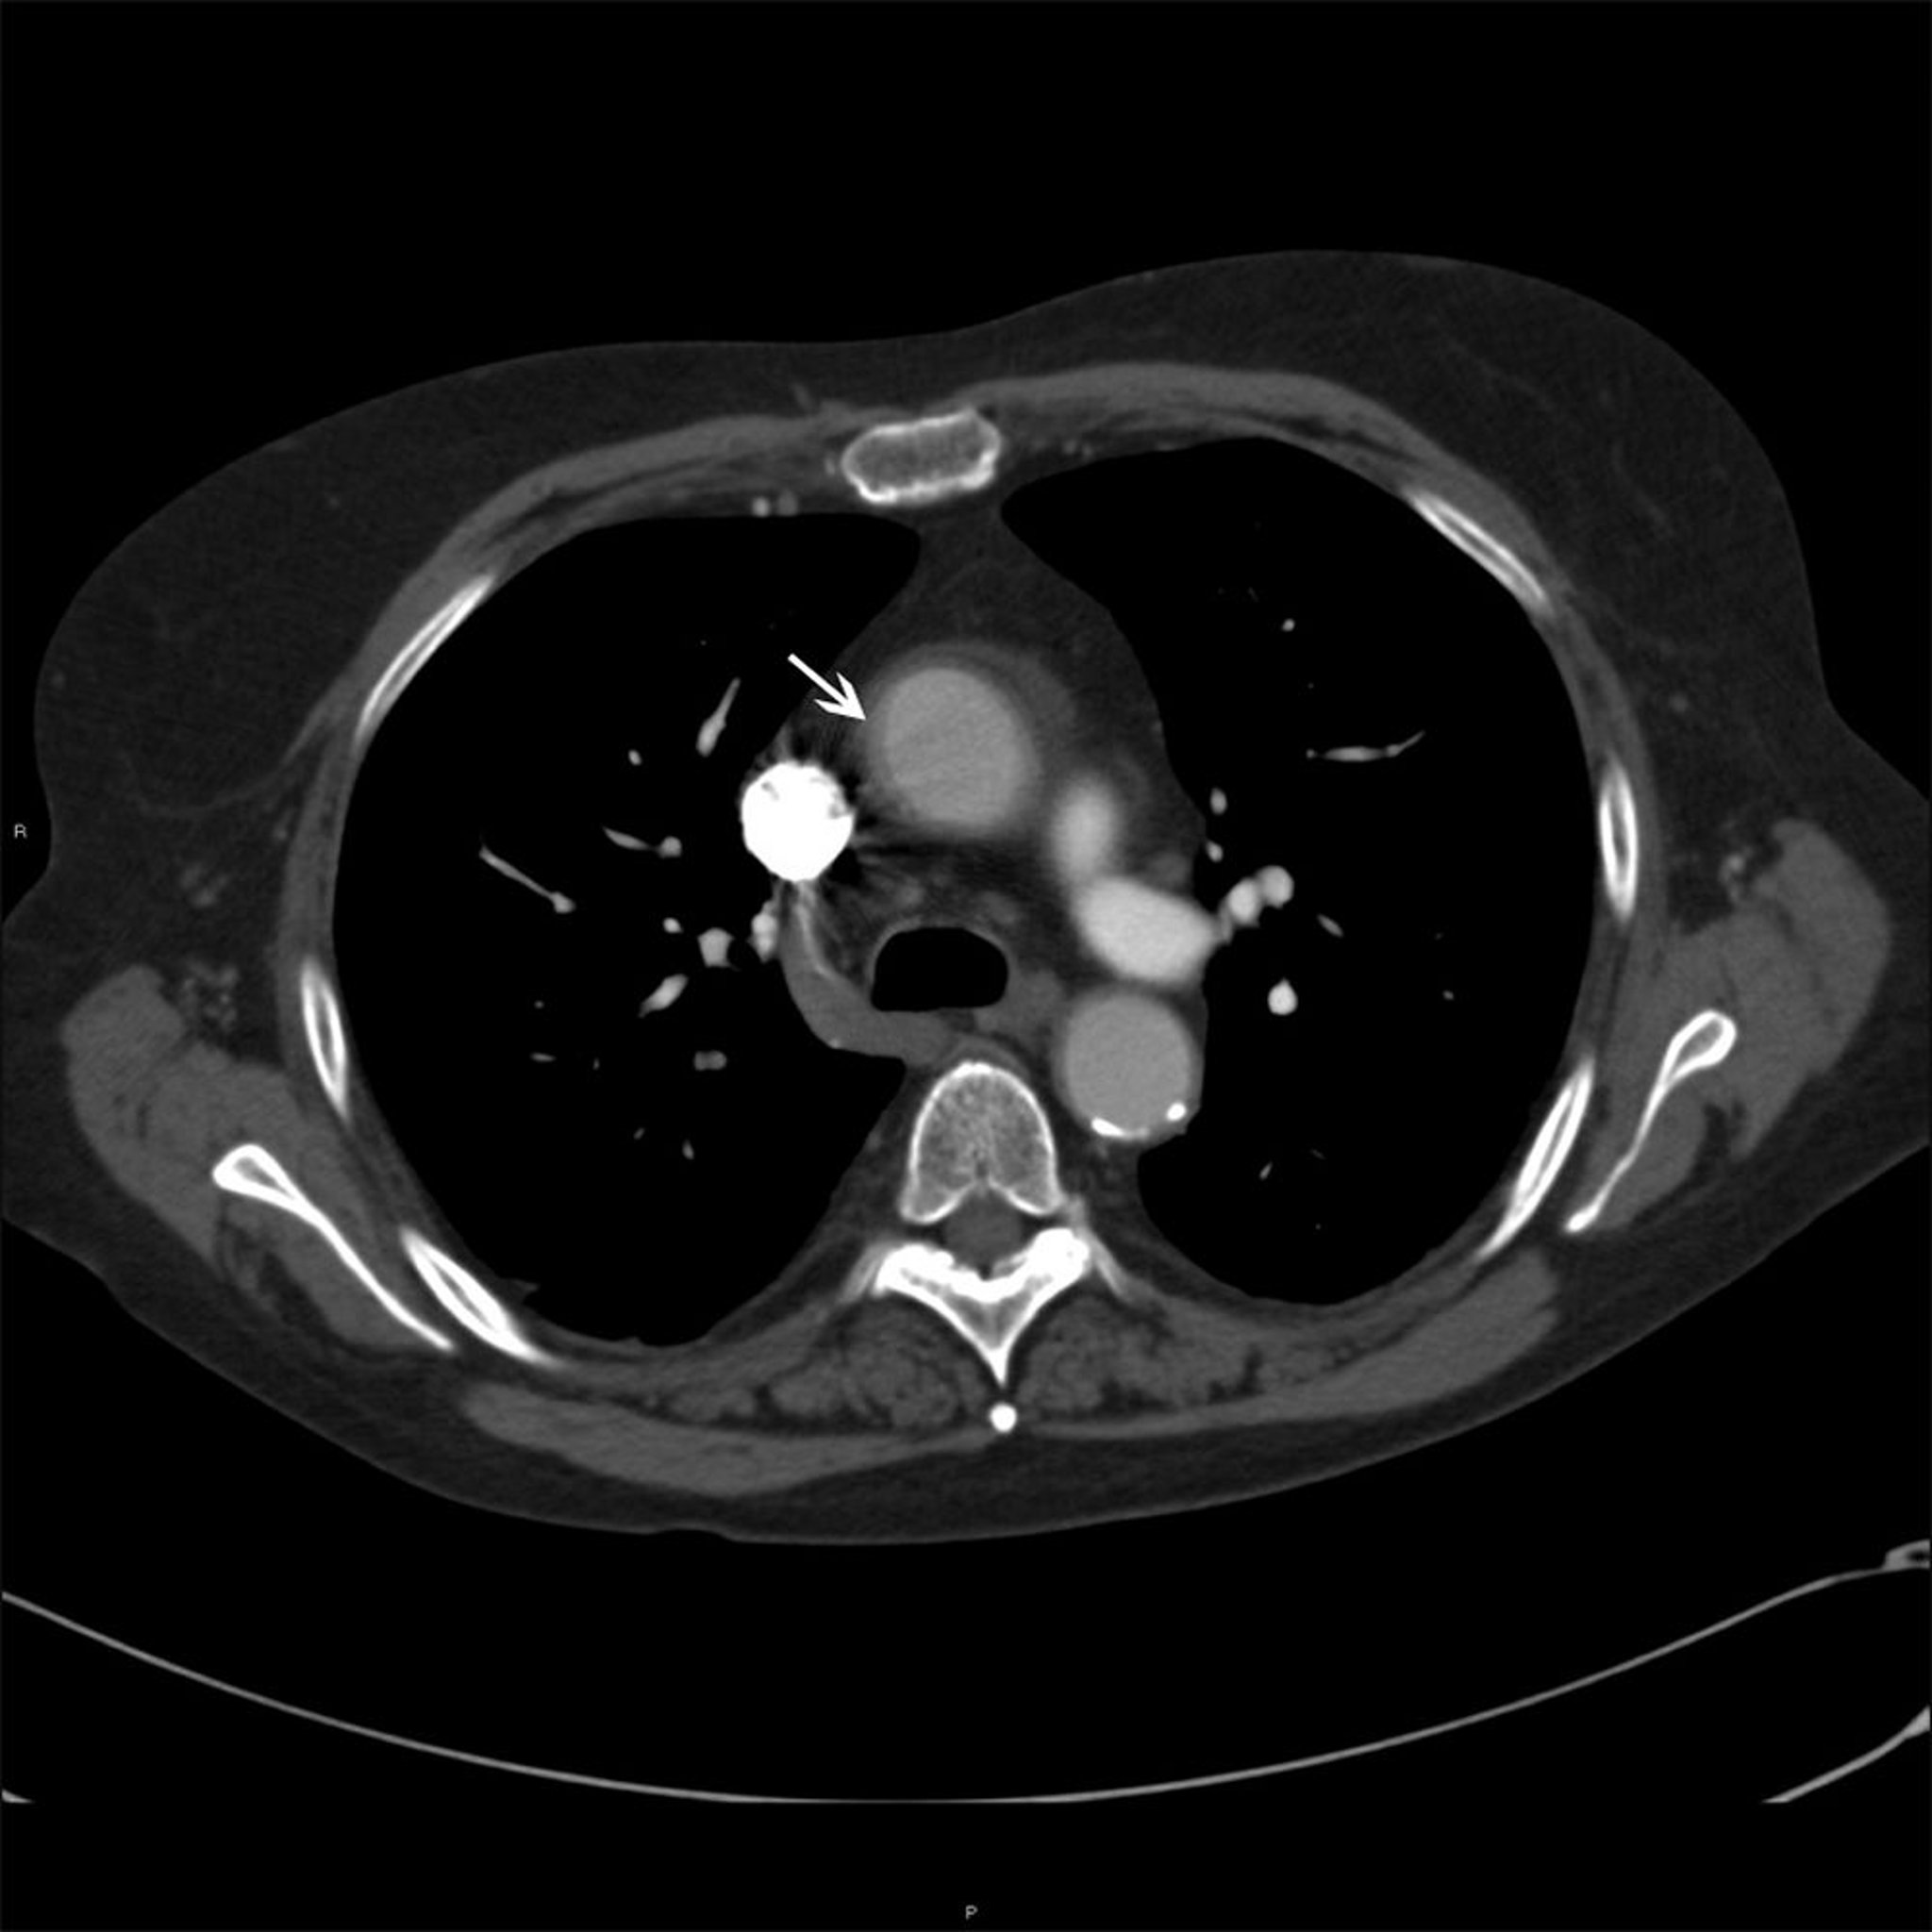

Aszendierende Aorta bei Patienten mit Takayasu Arteriitis

Dieses Foto zeigt eine Wandverdickung (weißer Pfeil) der aufsteigenden Aorta bei einem Patienten mit Takayasu-Arteriitis.